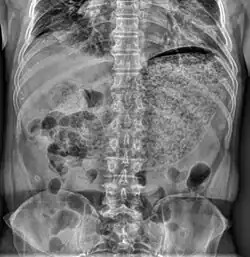

Simple abdominal X-ray shows gastric distension with a large amount of material in the stomach, suggesting severe gastric hypomotility | |